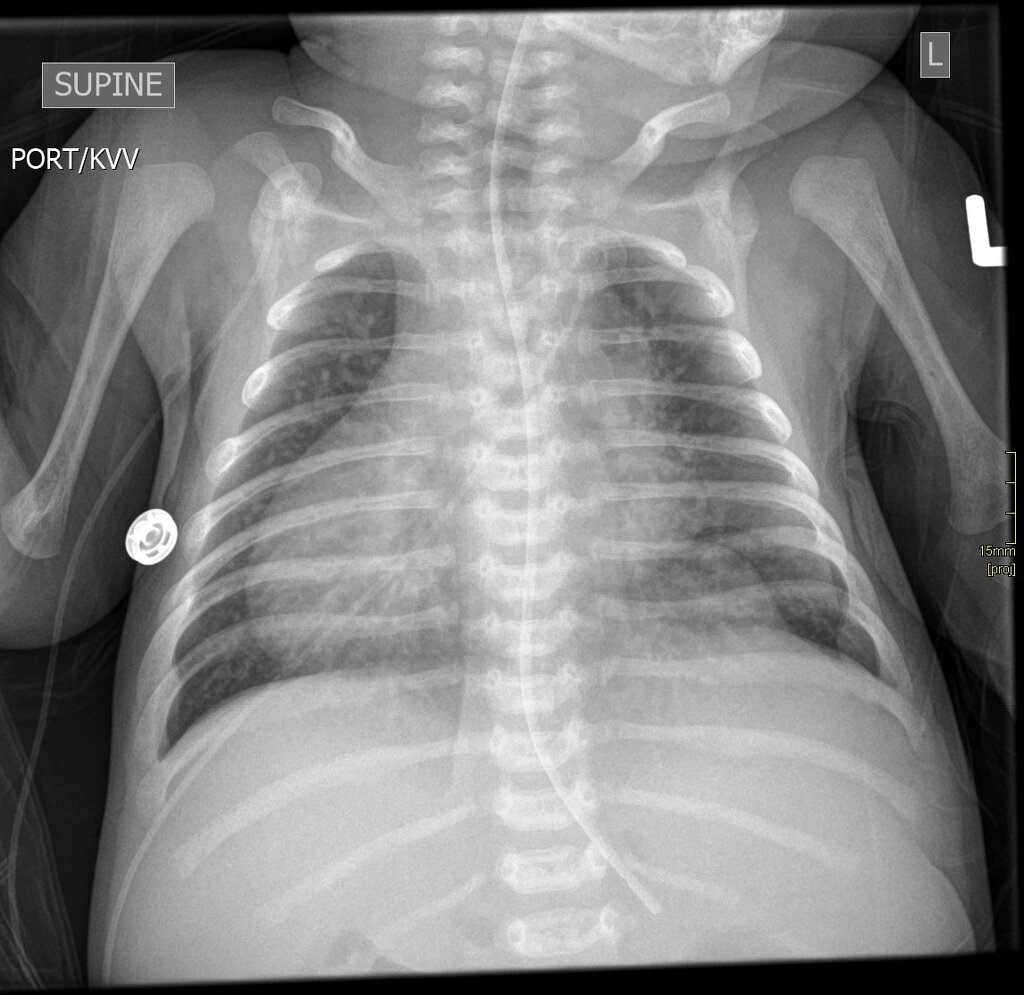

Salut les amis 🎉 Homme, 78 ans, post-SCA. Scanner car douleur abdominale, des coupes passent au niveau du thorax. Que voyez-vous ? 🌐 Interprétation : https://t.co/klcvSsNL84 #Radiologie #EDN